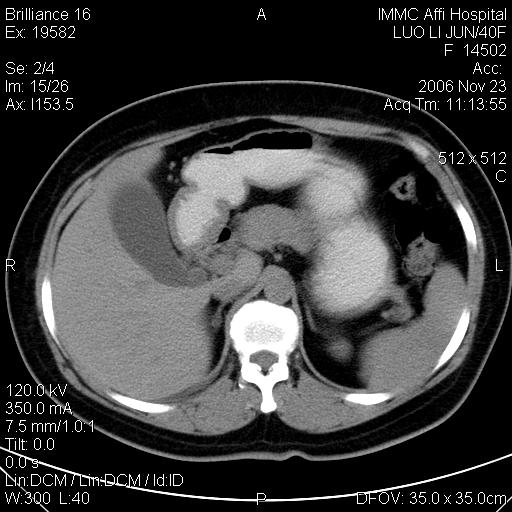

标题: CT5664:我也发一个肝脏的片子大家看看

很典型的肝癌。

典型肝癌

肝癌

速升速降,典型肝癌.

典型肝癌.

是啊,典型的早出早归!

快进快出典型肝癌.

符合肝癌的增强特征。支持肝癌!

病灶好圆!可能恶性度不高。

不能除外肝细胞腺瘤吧,还是得结合病史。

很好的片子,可惜增强做的比较失败,a期时间没有把我好,实际到了静脉早期了,否则会更典型。

最终考虑是肝腺瘤